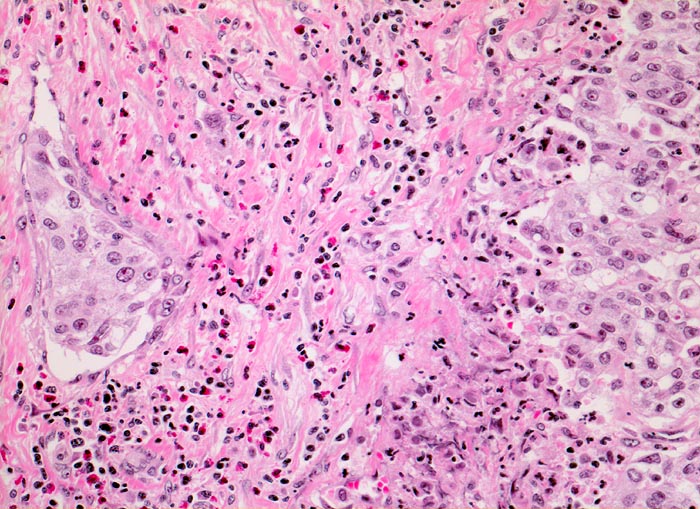

• Tumorzellkerne mit ausgeprägter Pleomorphie und Hyperchromasie sowie prominenten Nukleolen. Fehlende polare Ausrichtung der Tumorzellen. Zahlreiche Mitosen und Apoptosen.

• Kleinherdige Tumornekrosen.

• Invasion der Lamina propria (Tumorfragmente links): Kleine Tumorzellgruppen oder Einzelzellen haben die Basalmembran an wenigen Stellen durchbrochen und liegen in der Lamina propria.

• Begleitendes dichtes gemischtes Entzündungsinfiltrat.